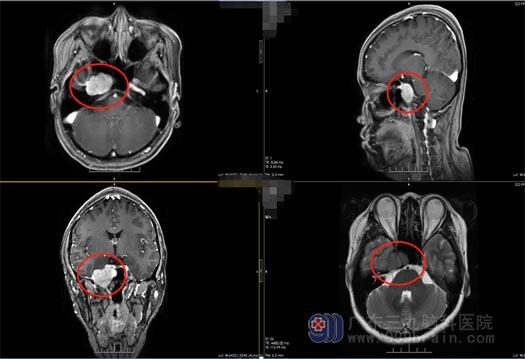

小方,三周前开始出现双眼重影,刚开始觉得只是眼部问题,并不太过在意,而且自己还年轻,才29岁,不会有太大问题。在之后的两个星期里双眼重影的问题不但没有减轻,而且出现了头部疼痛症状,这才想起来到医院去检查,头颅MR结果提示:右侧鞍旁占位。

找到广东三九脑科医院副院长鲁明后,经我院专业检查,初步诊断为脑膜瘤,该部位的脑膜瘤以眼的症状为主。考虑患者年轻,既要切除病灶,同时也要保护好神经功能,如何以最小的创伤解决患者的问题,鲁明带领神经外五科王国良主任团队进行了讨论。

最后一致决定采用“内镜辅助下经鼻行右侧鞍旁海绵窦内占位性病变切除术”,不用开颅,从鼻孔进入。内镜下见肿瘤呈灰白色,质软,全切肿瘤,手术顺利结束。术后,小方视物重影消失,未出现术后并发症,一周后满意出院。